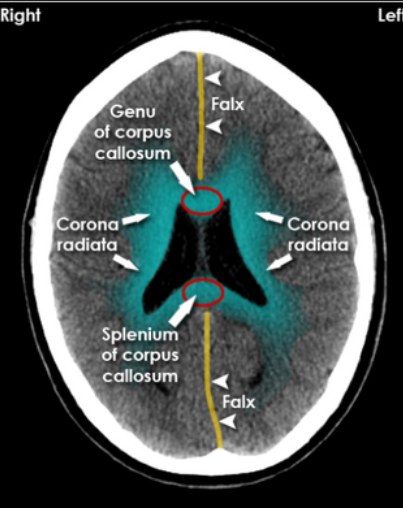

White Matter Radiology Key

Brain Ct Neurologyneeds Com

Corona Radiata Brain